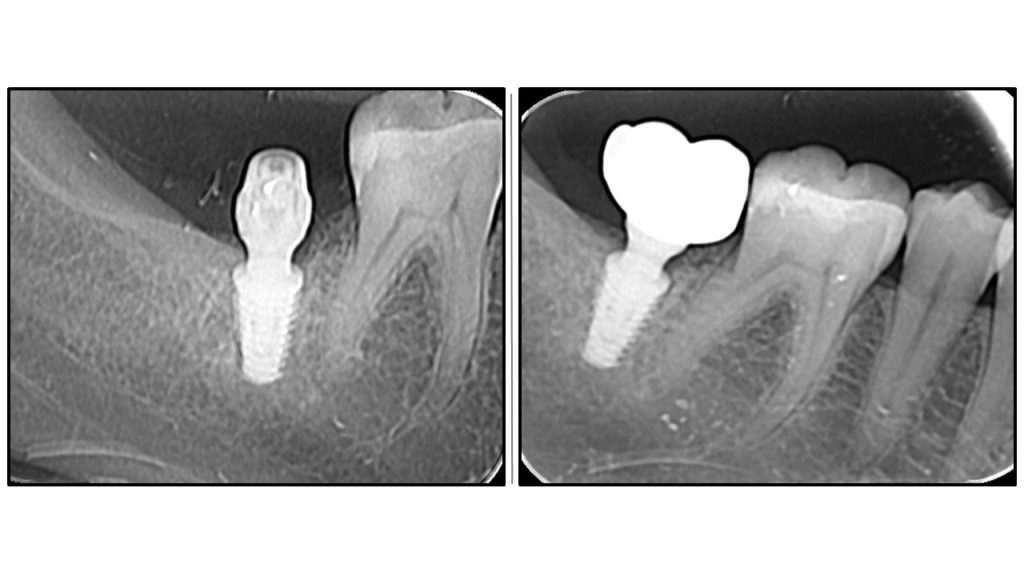

Радиографска анализа: стабилност костине крошне